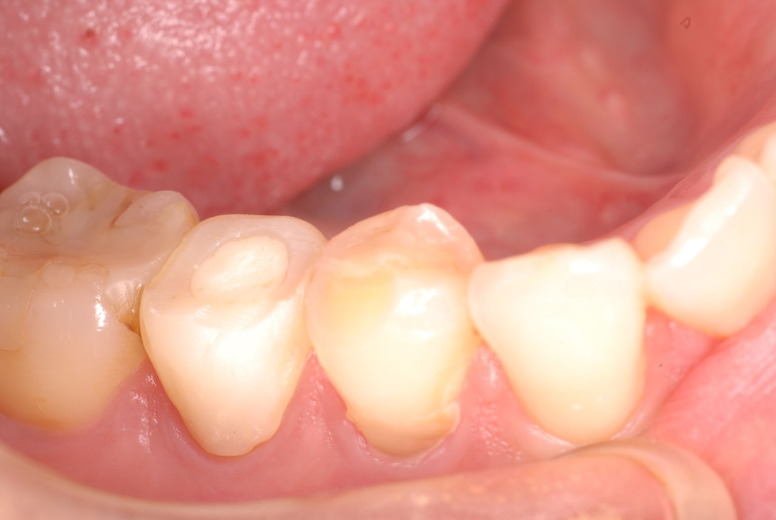

14年歯前、歯の神経が腐り、神経を除去したまま来なくなった現在大学生の女性

歯周病になっていましたが、少し色が黄色くなっているだけで比較的綺麗な歯の状態です。

平成9年来院神経を取り、同時に歯周病の話をしてそのまま来なくなっていたかたですが、たまたま一部欠けてきました。それで来院。

平成9年![40af2ca7-s[1]](https://livedoor.blogimg.jp/netdental/imgs/0/d/0d02b3dc.jpg)